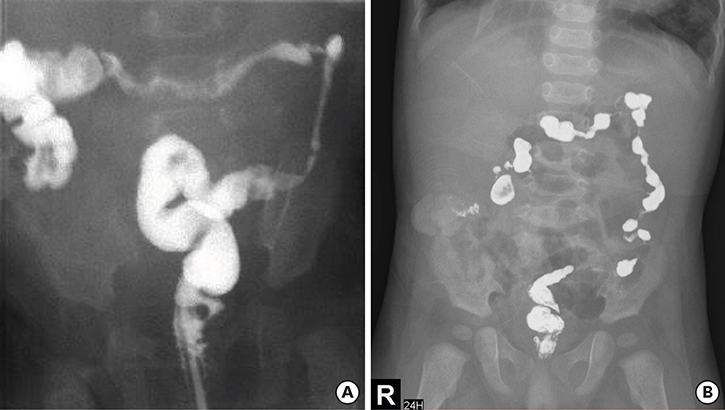

As aforementioned, the distal loopography should be performed before EC to evaluate the necessity of other operations. It can determine post-operative complications and whether excrement is transitioned to the distal site [16]. Fig. 1A shows multiple stenosis of the large intestine following NEC. Fig. 1B shows a delayed contrast passage in the colon after 24 hours. In order to confirm the accuracy of loopography, Koivusalo et al. [16] have compared preoperative loopography and actual surgical findings in 25 patients with NEC and SIP. As a result, the positive predictive value was 100%. However, the sensitivity was only 38%. Specificity and negative predictive value were 100% and 77%, respectively. This means it is difficult to predict anastomosis complication through preoperative distal loopography. For the patient in NEC, distal loopography should be performed to evaluate postoperative stricture that can be shown in 32%–40% of patients [917].

Fig. 1

(A) Colonic stricture after necrotizing enterocolitis. This colon study was obtained 3 month later after enterostomy formation. (B) A delayed evacuation of contrast agent with meconium-related ileus.